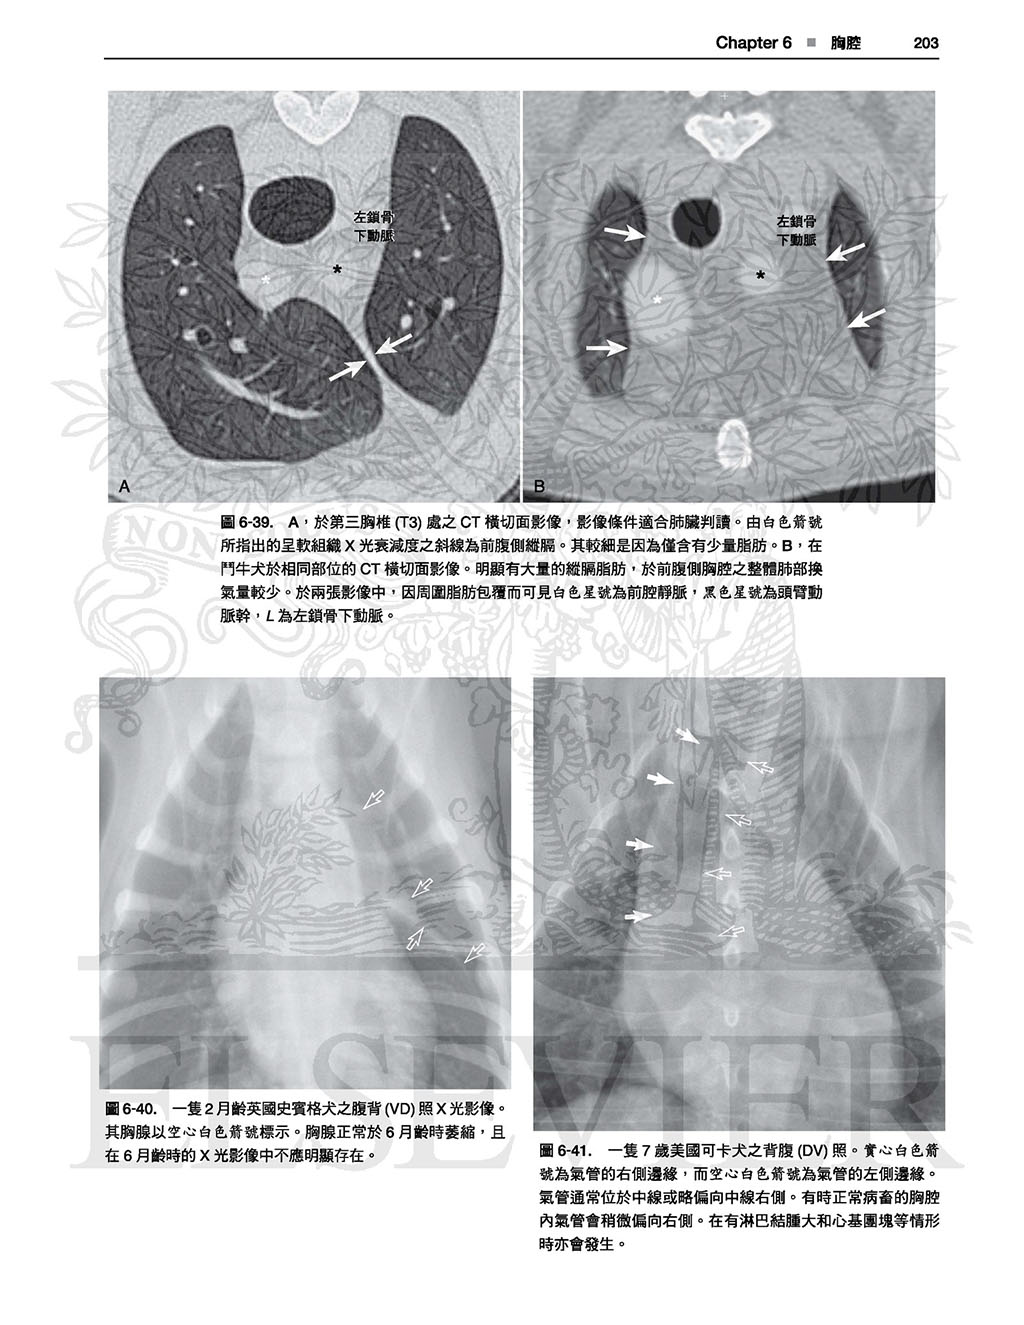

本書並不只是單純的圖譜,各身體部位皆有文字敘述,

因此有助於讀者理解各構造於X光影像學中如此呈現之原因,且提供了讀者對於X光影像學原理基礎性的理解,

有助於對其他正常變異之辨別,雖然可能需要讀者花點心力與圖譜對比使用,但對於判讀能力會有不小的幫助。(本書前言)

以這本詳盡的圖譜學習犬貓正常放射線解剖學的範圍。精通本書將可使診斷更精確並達到更佳的治療效果!

全書皆為高對比的數位影像,除提供正常影像的深入判讀外,亦提供常見且易被誤判為疾病的正常變異;另外並提供多張電腦斷層影像以強調某些結構之影像在放射線學下顯得如此獨特的原因。

本書不但含有豐富圖片,身體各部份皆附上文字描述以協助讀者了解放射解剖學原則,讀者可舉一反三、甚至能以此理解未包含於本書的正常變異。

最新!更多的電腦斷層影像,詳細解釋某些結構形成獨特放射線學影像的原因。

.詳盡的文字說明及圖片標示

.未標記的原始圖片及標示後的圖片比對

最後,本書並不只是單純的圖譜,各身體部位皆有文字描述,因此有助於讀者 理解各構造於X光影像學中如此呈現之原因,且提供了讀者對於X光影像學原理基礎性的理解,有助於對其他正常變異之辨別,雖然可能需要讀者花點心力與圖譜對比使用,但對於判讀能力會有不小的幫助。

全書皆為高對比的數位影像,除提供正常影像的深入判讀外,亦提供常見且易被誤判為疾病的正常變異;另外並提供多張電腦斷層影像以強調某些結構之影像在放射線學下顯得如此獨特的原因。

本書不但含有豐富圖片,身體各部份皆附上文字描述以協助讀者了解放射解剖學原則,讀者可舉一反三、甚至能以此理解未包含於本書的正常變異。

最新!更多的電腦斷層影像,詳細解釋某些結構形成獨特放射線學影像的原因。

.詳盡的文字說明及圖片標示

.未標記的原始圖片及標示後的圖片比對

最後,本書並不只是單純的圖譜,各身體部位皆有文字描述,因此有助於讀者 理解各構造於X光影像學中如此呈現之原因,且提供了讀者對於X光影像學原理基礎性的理解,有助於對其他正常變異之辨別,雖然可能需要讀者花點心力與圖譜對比使用,但對於判讀能力會有不小的幫助。